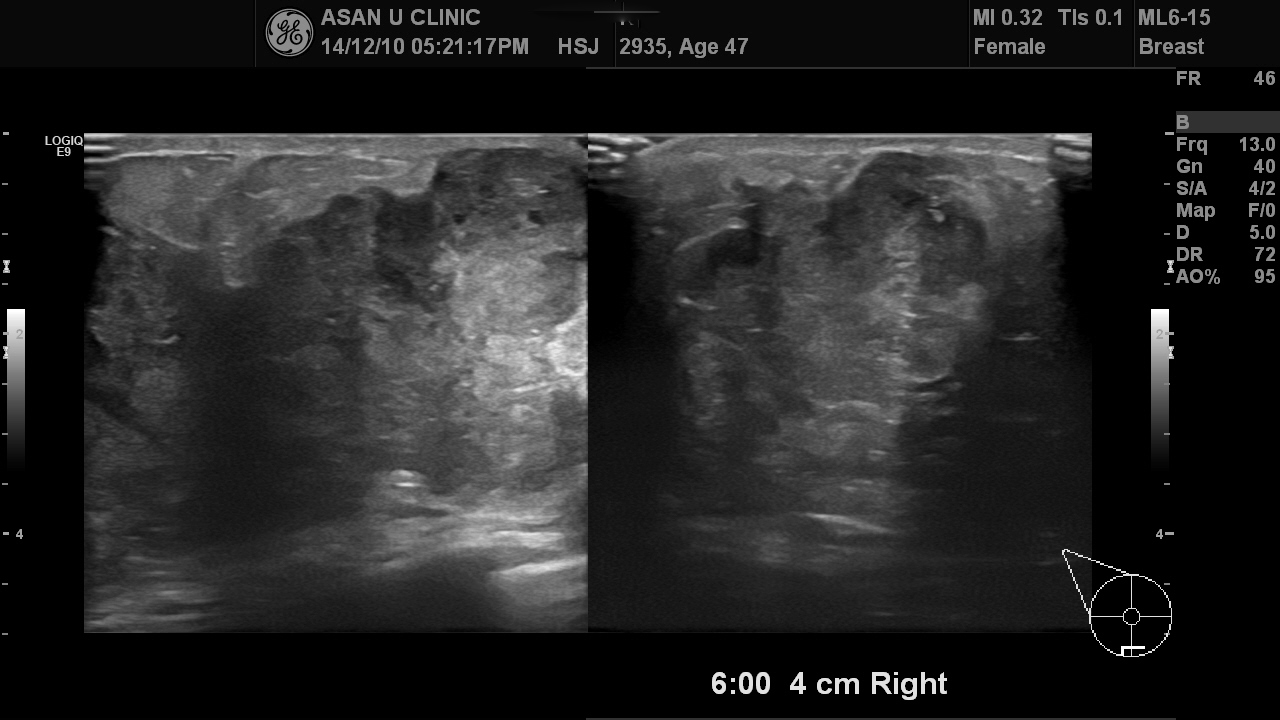

5년전부터 만져지던 몽우리가

최근 더 커지는 것 같아 검사위해 내원하신 47세 여성분입니다.

우측 유방의 젖꼭지부위 근처 유륜부에서

하내측으로 피부가 팽팽라게 땡겨질 정도로 튀어나온 덩어리였습니다.

중심핵생검을 하여 점액암이 진단되었으며

유방에 혹이 심한데 비해 겨드랑이에 림프절은 심하게 비대된 상태는 아니라

다행입니다.